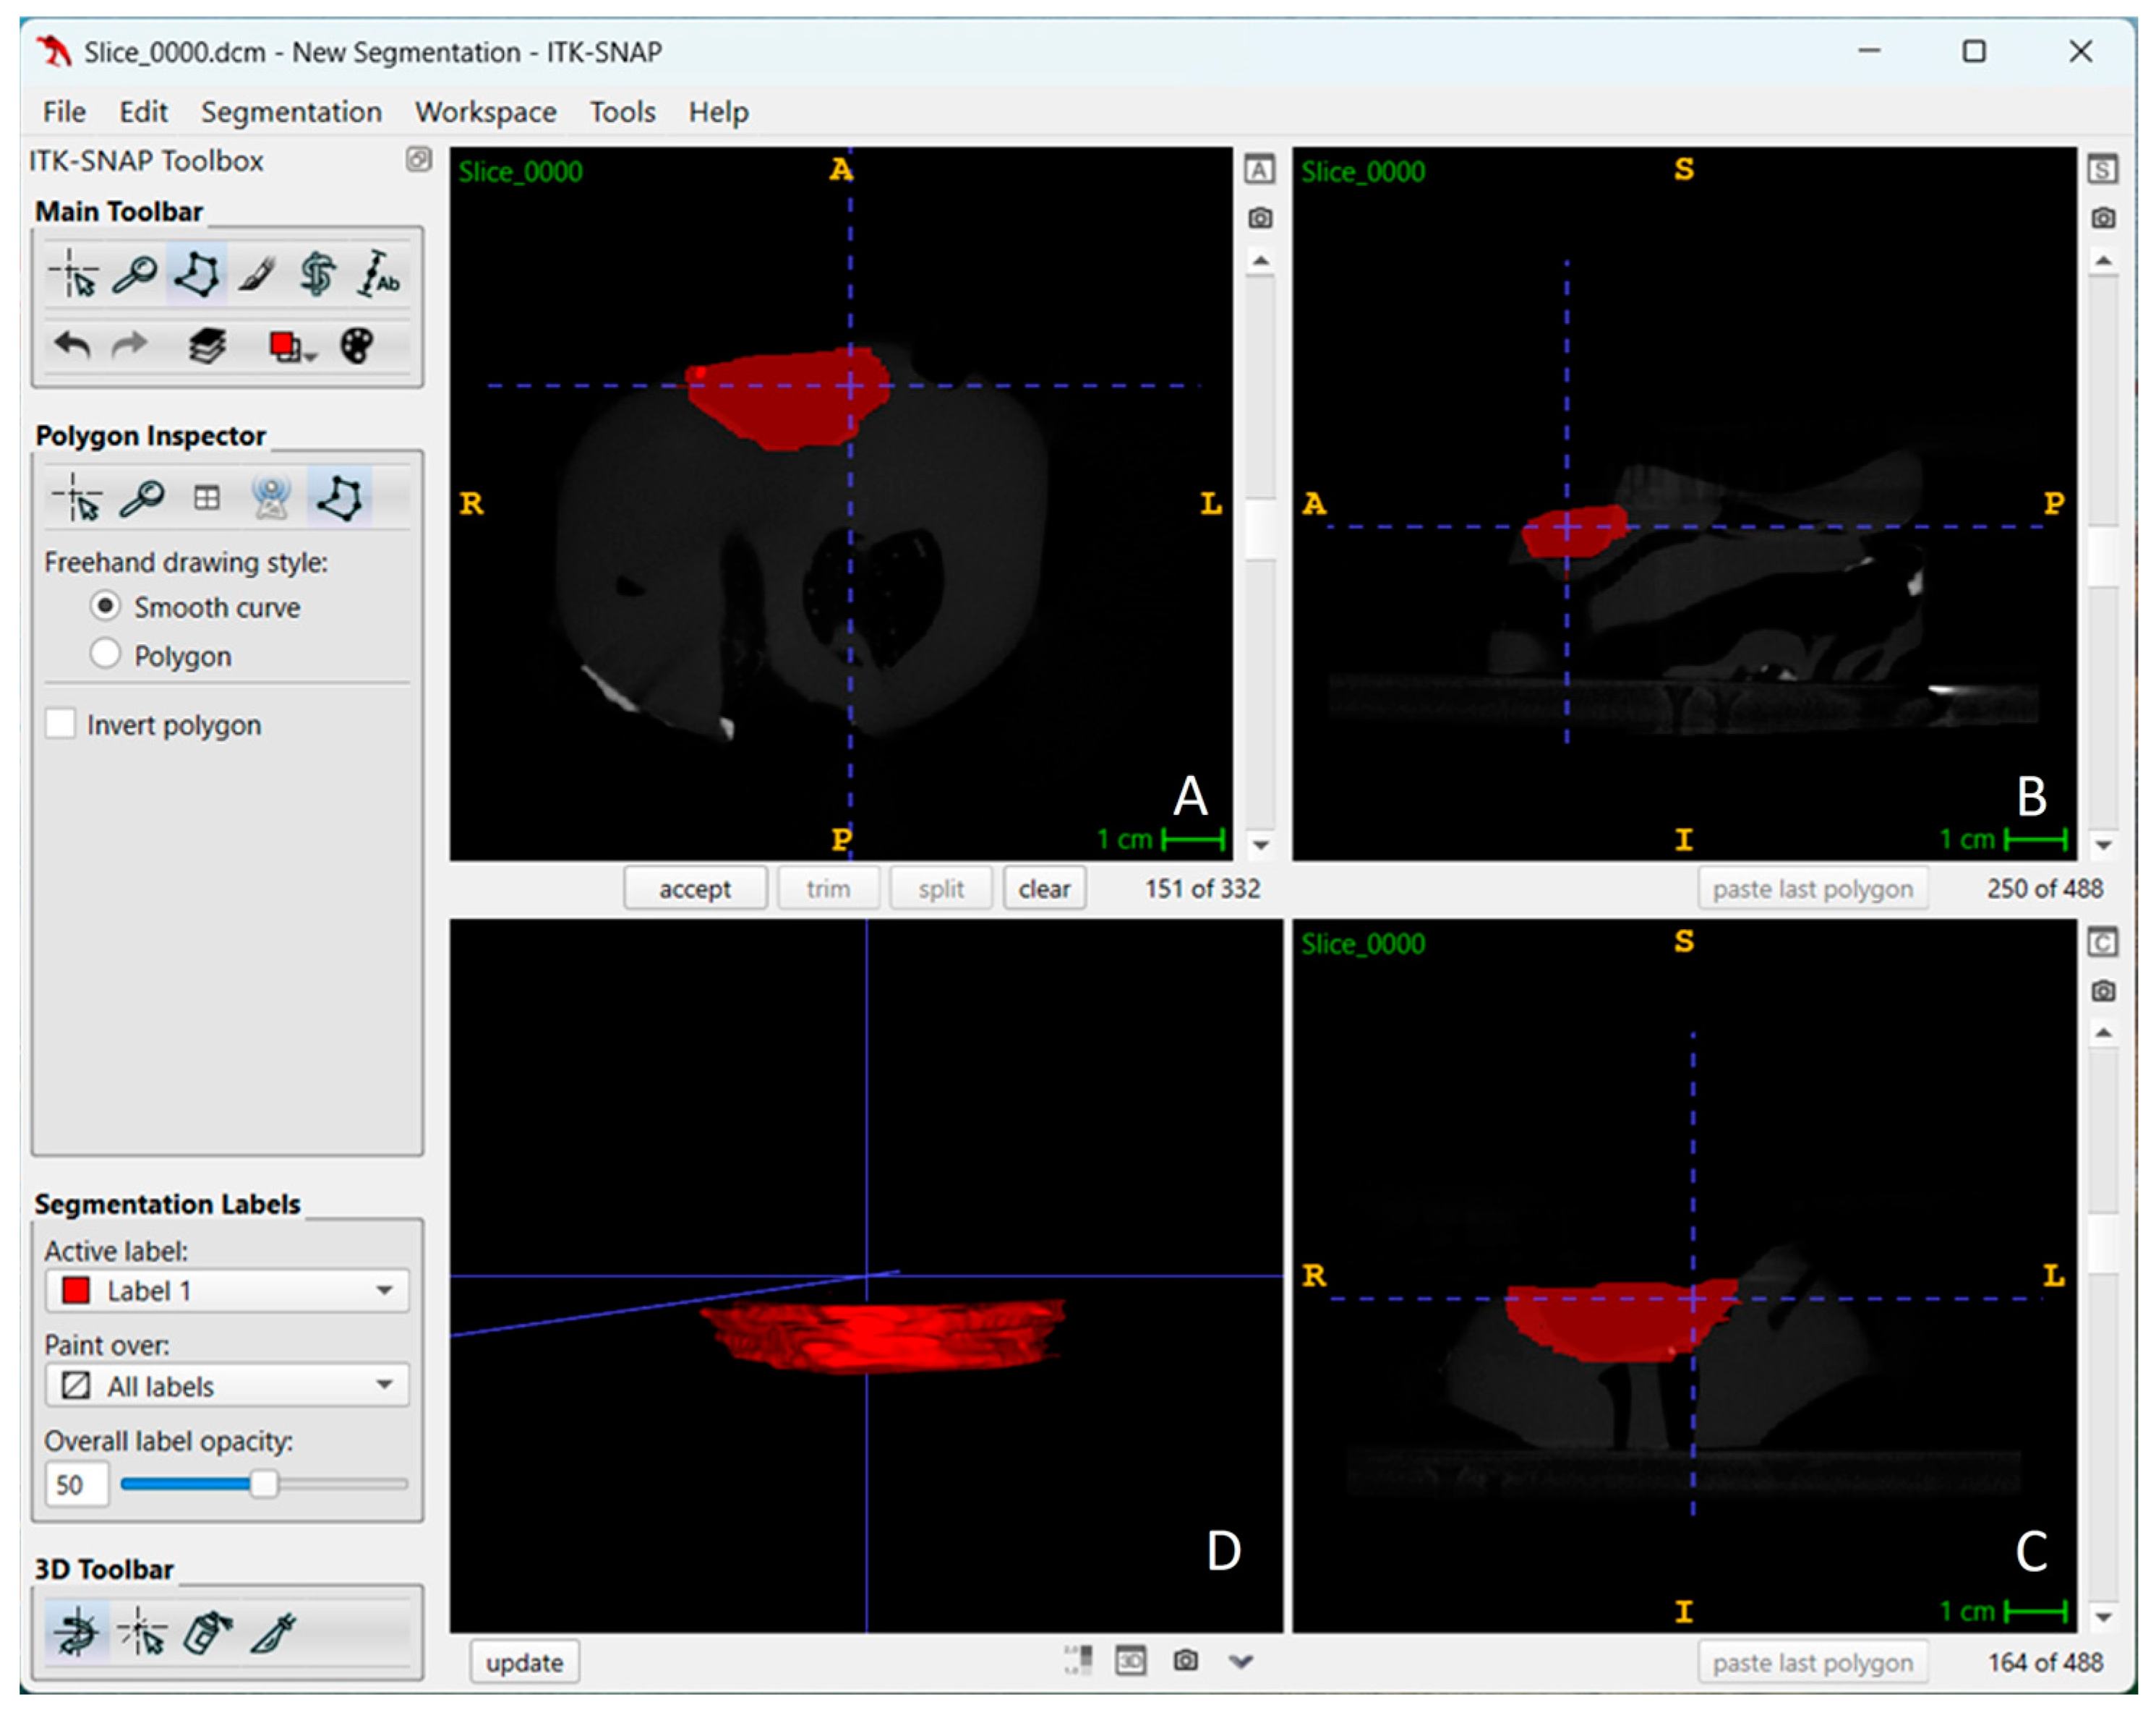

2. Materials and Methods